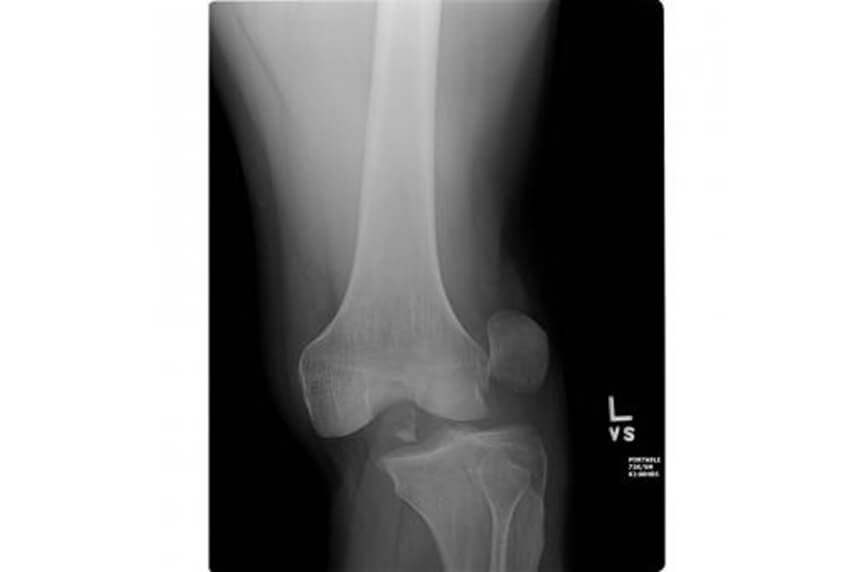

- Tibial Plateau Fracture

These injuries are frequently observed in sports, especially skiing.

Patients usually report pain, swelling, and limited knee movement, similar to LCL injuries, though without the associated instability.

Surgery is very rarely recommended in this situation, with a period of immobilization followed by a sufficiently long sports rehabilitation program to treat knee pain, allowing the patient to lead a normal life.